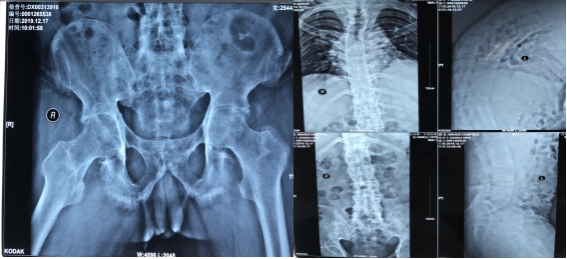

家住甘肃省文县堡子坝乡的王先生10年前因腰部疼痛被诊断为强直性脊柱炎,当时疼痛不明显、腰椎活动不受累,故并未在意,也未系统诊治。后来,症状逐渐向颈椎、双侧髋关节发展。约7年前,王先生于四川大学华西医院检查,被诊断为“强直性脊柱炎”,经过药物控制治疗后脊柱症状趋于稳定。

然而2年前,王先生双侧髋关节开始疼痛,多处就诊,诊断为强直性髋关节炎。之后又逐渐出现髋关节活动度降低等症状,于文县当地医院住院拟行关节置换相关手术治疗,后因强直性脊柱炎导致麻醉困难,髋关节置换手术未能如期进行。

陈天健主任进一步补充道,此例手术难度不仅仅在于手术,更在于各项术前准备工作中,病人脊柱广泛融合导致无法平卧,因此术前检查、术中麻醉、术中体位等都具有相当大的难度。